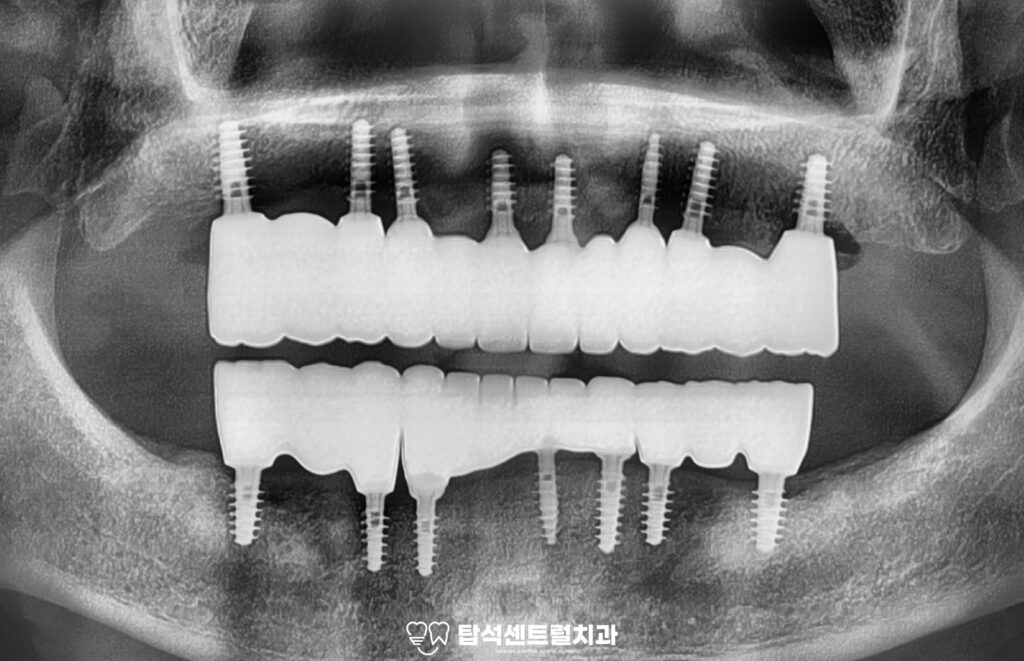

전체 임플란트 치료의 마지막 단계로,

최종 보철을 장착하였습니다.

발치 후 3개월 동안의 골유착 기간을 거쳐

고정력을 확보하였으며

임시보철을 사용하면서 적응된

치아의 고경과 높이에 맞춰

최종 보철이 정밀하게 제작된 모습입니다.